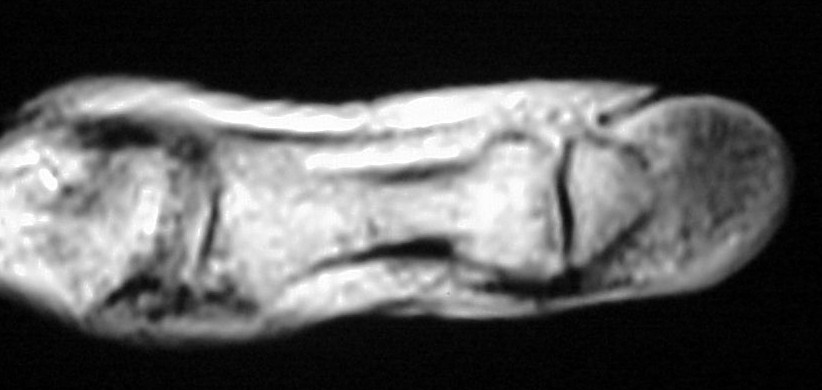

MRI demonstrated ill defined soft tissue replacement of the majority of the distal phalanx:

With contrast enhancement of the transformed area: